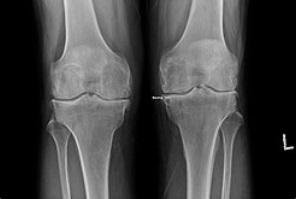

Артроз коленного сустава — дегенеративно-дистрофическое заболевание, причиной развития которого является поражение хрящевой ткани суставных поверхностей, принимающих на себя основную нагрузку при движении. Артроз — дистрофическое заболевание суставов, связанное с медленной дегенерацией и разрушением внутрисуставного хряща. При подтверждении диагноза «Артроз коленного сустава» или по научному (гонартроз) лечение назначается только врачом.

Важно отметить, что сам артроз не лечится. Если есть уже дегенеративные изменения в суставе — их никуда не деть. Здесь важнее выбрать метод лечения. Основной упор делается на «торможение дегенеративных изменений», т. е. торможение дальнейшего развития артроза.

Болезнь развивается в медленном темпе и может с годами доставлять небольшой дискомфорт. При дальнейшем развитие начинают нарастать болевые ощущения, появляется скованность в движениях, меняется форма колена.